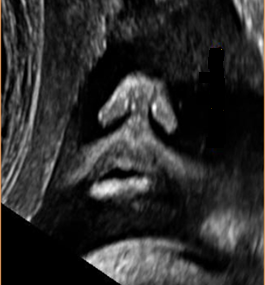

Above. Axial view of cleft lip and cleft palate demonstrating the alveolar ridge with tooth buds and the hard palate.

Serial axial/transverse views allow visualization of the nose down through the mouth to the lower edge of the mandible, thereby allowing assessment of the upper alveolar ridge, palate, tongue, and mandible. [13] Transvaginal ultrasound may be useful prior to 20 weeks.